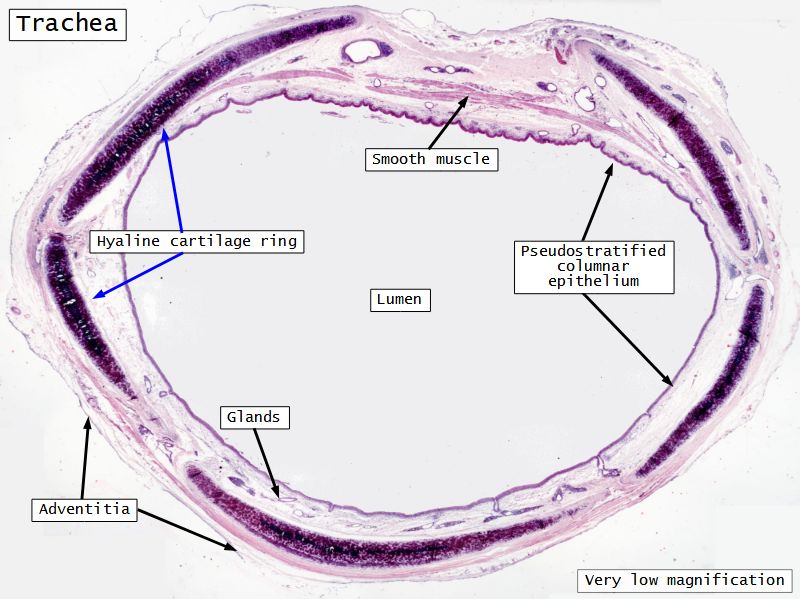

Respiratory epithelium

- Pseudostratified

- Ciliated

- Columnar

- Epithelium with

- 4 Cells

- Ciliated columnar cells

- Non-ciliated columnar cells

- Goblet cells

- Basal cells